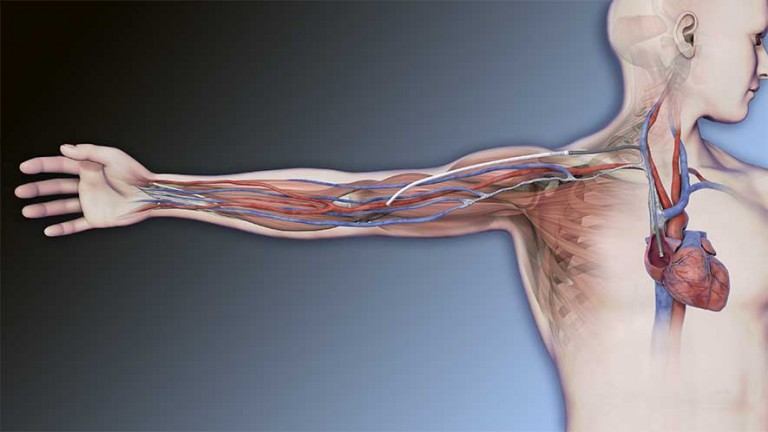

HEART ATTACK

A heart attack, also known as a myocardial infarction, occurs when heart muscle doesn’t receive enough blood. As time passes without receiving treatment, the more damage is done to the heart. The main cause of a heart attack is coronary artery disease (CAD). Researchers have found that throughout life, men are about twice as likely as women to have a heart attack.

Learn more about heart attacks. Explore our Cardiac Portfolio, including our radial sheaths, catheters, wires, and compression devices.

MERIT PRODUCTS